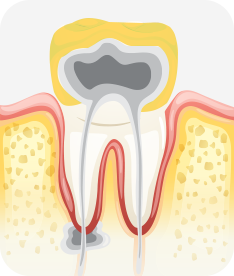

신경치료

자연치아를 살라기 위한 가장 기본적이고 중요한 치료입니다

치아 외상이나 충격, 깊은 충치 등의 이유로 치아 내부의 신경과 세포 조직에 염증이 생겼을 경우, 이 를 제거하고 소독하여 생체친화적인 특수 재료로 신경관을 충전해 치아의 기능을 유지할 수 있는 중요한 치료입니다.

사람마다 치아의 모양이나 치아 내부 신경관의 모양도 다 다릅니다.

3차원적인 신경관 내부를 치아 밖에서 도달하여 뿌리 끝까지 정밀하고 정확하게 치료해야 하는 신경치료는 가장 기본적인 자연치아 살리기 치료이자 고난이도 치료입니다.

치아신경 염증

충치가 심해져 치아 뿌리까지 신경 염증이 발생함

신경소독

충치를 제거하고, 치아 뿌리 끝까지 신경관 내부의 염증 물질들을 제거하고 소독함

신경치료 완료

소독된 신경관을 생체친화적인 재료로 충전한 후 보철치료를 함